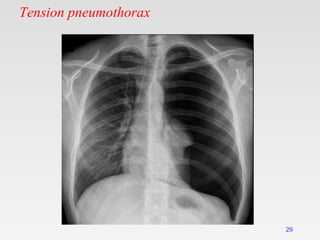

Tension pneumothorax

29

Radiological manifestations of large pneumothorax

• Mediastinal shift,

• Flattening of the hemidiaphragm &

• Lung collapse.

It is more common with

• Positive pressure ventilation &

• Traumatic pneumothorax.